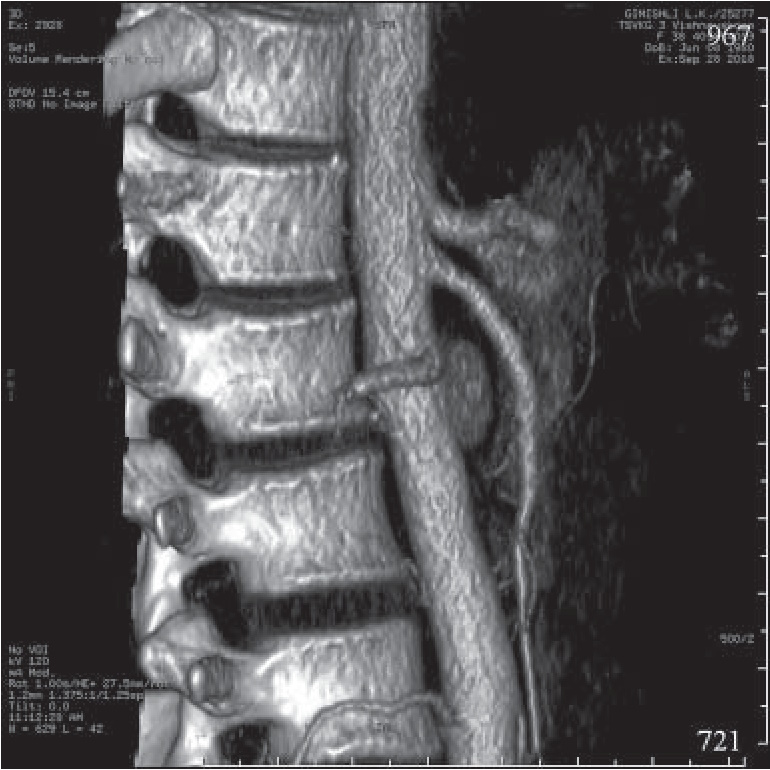

Проведенное цветное дуплексное сканирование непарных висцеральных ветвей брюшной аорты показало наличие экстравазальной компрессии ЧС (стеноз на выдохе 50–60%), что позднее подтвердила компьютерная томография (КТ) брюшной полости с контрастированием (рис. 1). На консилиуме врачей госпиталя с целью определения показаний к хирургическому лечению принято решение о проведении ангиографии висцеральных ветвей брюшной аорты. Выполненная аортография позволила определить сужение проксимальной трети ЧС около 75% (рис. 2). На повторном консилиуме было принято решение о проведении плановой хирургической декомпрессии ЧС.

Рис. 1. КТ-ангиография брюшной аорты от 08.09.2016 г. (а), КТ-картина экстравазальной компрессии чревного ствола до 60% (б)